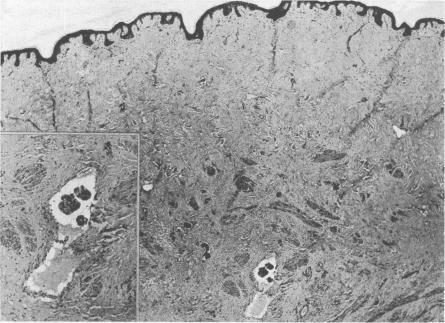

Haagensen C D, Stout A P

Ann Surg. 1943 Dec;118(6):1032-51. doi: 10.1097/00000658-194312000-00010.